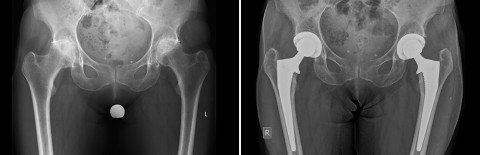

Fall 1: 74-jährige Patientin mit weit fortgeschrittener Arthrose beider Hüften

Zum Zeitpunkt der Vorstellung bei uns bestand bereits eine deutliche Einschränkung der Gehstrecke, teilweise auch nächtliches Erwachen aufgrund der Schmerzen. Die stärker schmerzende rechte Hüfte wurde über einen minimalinvasiven vorderen Zugang mit einem neuen Hüftgelenk versorgt. Aufgrund der positiven Erfahrung mit der Operation liess sich die Patientin 3 Monate später auch die Gegenseite operieren. Nach 3 Monaten war die Patientin wieder in der Lage, eine Städtereise ins Ausland mit längeren Gehstrecken beschwerdefrei zu absolvieren.

rechts: Röntgenbild 6 Wochen nach der zweiten Operation der linken Hüfte. Alle Komponenten wurden zementfrei im Knochen verankert